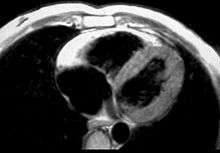

Photomicrograph of an ARVC heart. | |